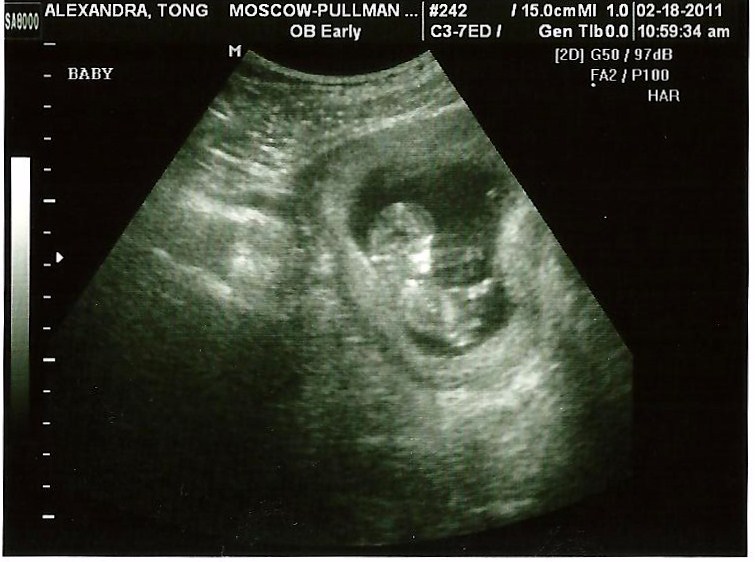

The baby was jumping around like crazy during the ultrasound, waving its little t-rex arms all over the place and bouncing up and down. It was hilarious. I’m not going to lie, I was really, REALLY nervous about this ultrasound. I kept having this awful feeling that something was wrong, but hearing the perfect heartbeat (162 beats per minute!) It took a while for the baby to calm down enough to get a clear picture, but it was good to know that the baby was an active little guy/girl!

I have nothing for a name but that’s a really good ultrasound pic! 🙂 Congrats.

aw, congrats! So glad everything looks good. With Jeremiah, I was a nervous wreck the day of the first ultrasound – I didn’t sleep the night before and was super edgy. We love them so much even before we see them! And, this is a really great first ultrasound picture – I’ve never really seen a baby this small look so human!

Alicia, I was SO surprised to see it look so much like a fully formed miniature human! I guess I am glad I waited a few weeks longer to get my ultrasound! (And then found out I was more than a week farther along than I thought!)